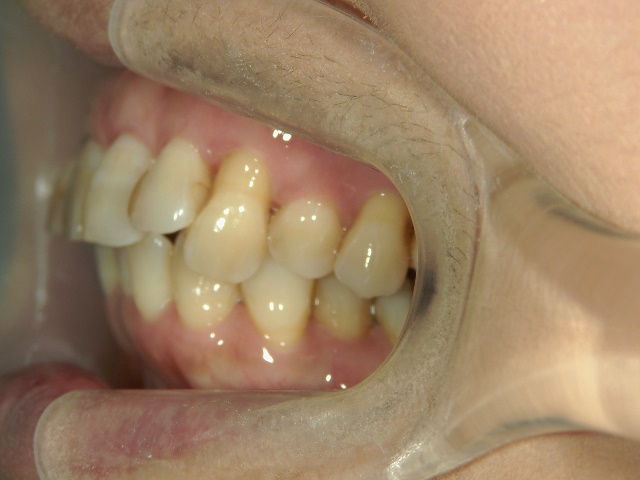

全顎ワイヤー矯正 症例(6

)

58歳女性 浜松市浜北区

在住

治療期間11

ヶ月